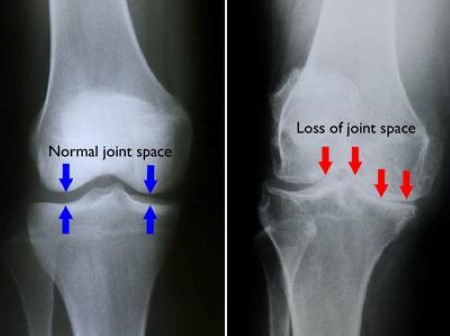

Total knee replacement (TKR) is a surgical procedure in which a damaged knee joint is replaced with an artificial joint, known as a prosthesis. It is usually performed for severe arthritis or other conditions that cause significant pain and limitation in knee function. After the surgery, the patient undergoes a period of rehabilitation to restore mobility, strength, and function. Here are some indications, precautions, and rehabilitation guidelines for total knee replacement:

1. Severe osteoarthritis or degenerative joint disease